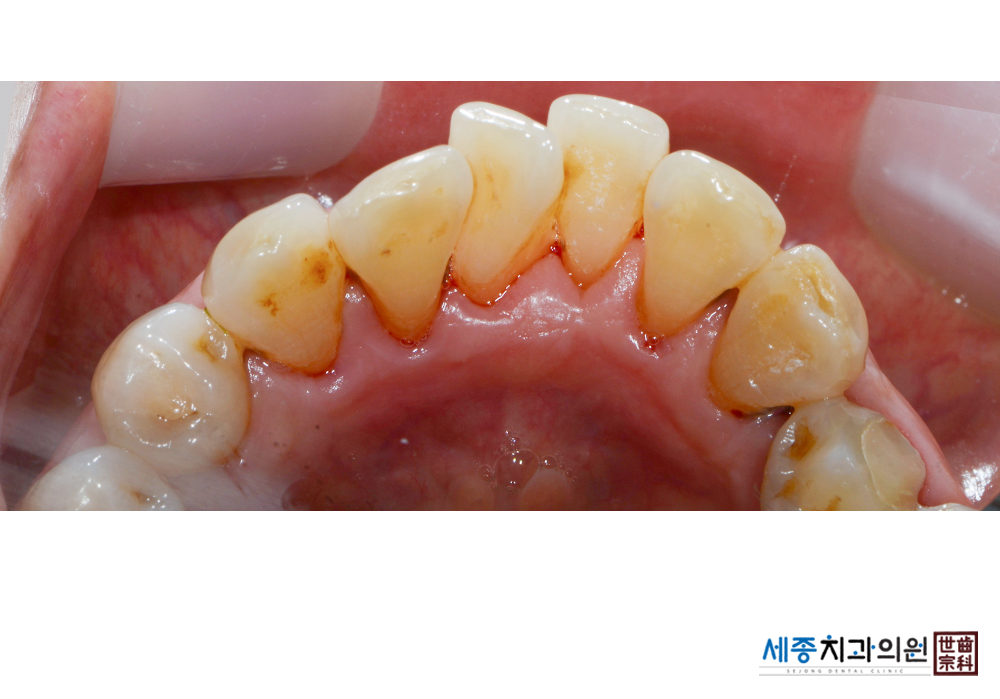

[스케일링] 치주질환 예방 스케일링 치료

치료전 : 2019-01-11

가글마취&저주파 스켈러를 사용한 스케일링